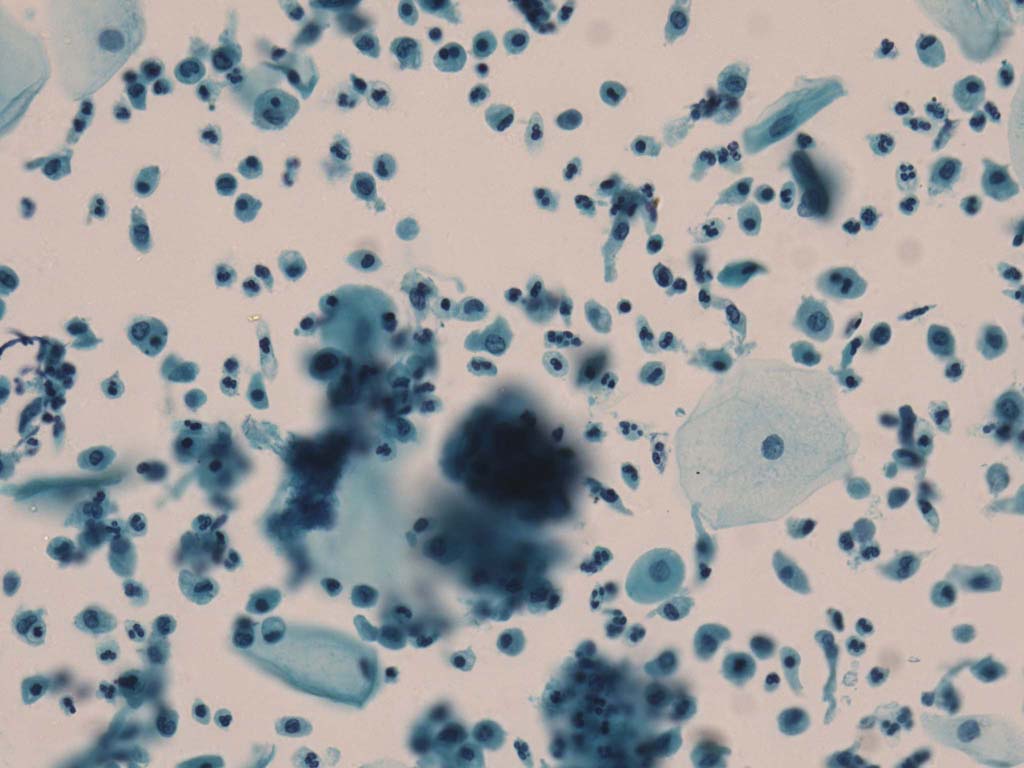

A good image fusion method should contain the following properties. First, it preserves both the details of small size objects and the integrity information of large size objects in the fused image, even in the case of the size of the interested objects varying largely in the image. For example, the cervical cell images from the microscope contain both small size isolated cells and large size agglomerates, which are both useful for cervical cytology [5]. Second, it should be efficient enough to handle large-scale data. For instance, it needs to process thousands of fields of view (FoV) in an acceptable time for the whole slide scanning in digital cytopathology [6], which requires to fuse a series of high resolution images captured at each FoV in a very efficient way. Third, it does not produce obvious artifacts. Despite being studied extensively, to our best knowledge, existing fusion methods may not meet these requirements simultaneously.

To demonstrate the effectiveness and efficiency of the proposed image fusion method , we conduct a set of comparative experiments on three image datasets. The first is composed by 8 pairs of multi-modal medical images and the second one contains 15 pairs of multi-focus gray or color natural images. These two datasets are often used in many related papers and some examples are shown in Figure 3(a) and Figure 3(b). The third one is a new multi-focus cervical cell image dataset collected by ourselves, which consists of 15 groups of color images and each group contains a series of multi-focus cervix cell images with size of or , etc. Some source examples are shown in Figure 3(c). Our source code implemented in C++ along with the new multi-focus cervical cell image dataset is available online.

Figure 9, Figure 10 and Figure 11 show the comparative fused results of the multi-focus cell images shown in Figure 3(c). For clarity, we also present a closeup view in the right-bottom of each sub-picture in Figure 9 and Figure 10. As shown in the close-up views of Figure 9, the fused images based on DSIFT, IM, MWGF and BF methods are extremely blurred in the boundary and fail to keep the details of cell nucleus. Furthermore, the DTCWT and NSCT based methods produce halo artifacts in the fused images, while GFF and CNN based methods fail to preserve the small cell nucleus. LP-SR based method nearly works fine which keeps the most of the details of the small size cells, but the integrity of the clustered large size cells is damaged. Fortunately, in our proposed method, the integrity of the clustered large size cells is preserved and most of the isolated small size cells are maintained from the original images, which demonstrates the best visual quality.

Similarly, as shown in the close-up views of Figure 10, the fused images from DSIFT, IM, MWGF and BF are blurred and lose some nucleus details, while the results from DTCWT, GFF, CNN and NSCT produce halo artifacts. LP-SR based method can keep details well but also produces halo artifacts and other noise. Our method can preserve the focused areas of different source images well without introducing any artifacts. For the example illustrated in Figure 11, the fused images generated by DSIFT, DTCWT, IM and NSCT all fail to preserve the focused areas of different source images and result in extremely blurred images. The GFF, CNN, MWGF and BF based method introduces a lot of color distortion of the nucleus regions and the obvious halo artifact. The result of LP-SR based method is close to the one of our method but introduces some odd color distortion. Again, our method produces fused image which can preserve the focused areas of different source images well without introducing any artifacts.